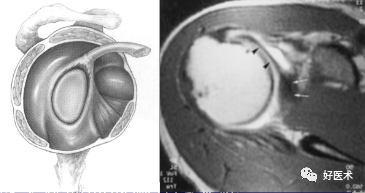

(3)盂唇韧带复合体

盂唇与关节盂缘的透明软骨相接,其作用在于增深关节窝并与盂肱韧带、关节囊和肱二头肌腱一起维持肩关节稳定性。

盂肱韧带包括上盂肱韧带(SGHL) 、中盂肱韧带(MGHL) 、下盂肱韧带( IGHL) 。它们都是关节囊前面增厚的部分。盂肱韧带与盂唇连在一起被称作盂唇韧带复合体。

2.盂肱韧带

-

包括上盂肱韧带(SGHL) 、中盂肱韧带(MGHL) 、下盂肱韧带( IGHL) 。它们都是关节囊前面增厚的部分,形成Z型结构。

维持肩关节的前向稳定。

SGHL向前走行与喙突相平行,止于小结节上方结节间沟区域并与喙肱韧带相融合。

MGHL在与盂缘邻近处向下走行,再以60°角横过肩胛下肌腱后止于小结节基底部。

IGHL:前束、后束和腋下陷窝部分。

Weitbrecht 孔; Rouviere 孔